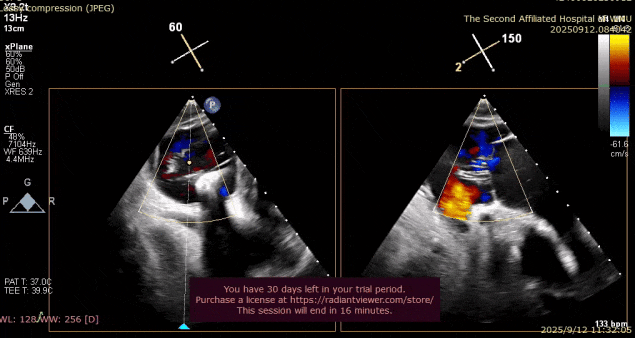

心脏超声示左室增大,二尖瓣2、3区脱垂伴重度反流(腱索断裂),Carpentier分型Ⅱ型,典型Barlow综合征表现;二尖瓣开放面积5.0cm²,3区瓣环内径31mm,前叶长22mm、后叶17mm,前叶收缩期关闭瓣体部分呈拱形突向左房腔,瓣膜游离缘对合欠佳,可见腱索断裂,长度9mm;2区瓣环内径32mm,前叶长22mm、后叶10mm,前后叶均可脱垂;三尖瓣重度反流。CDFI示瓣口重度偏心性反流,反流束沿主动脉后壁走行,肺静脉收缩期可见反向频谱。

术前反流